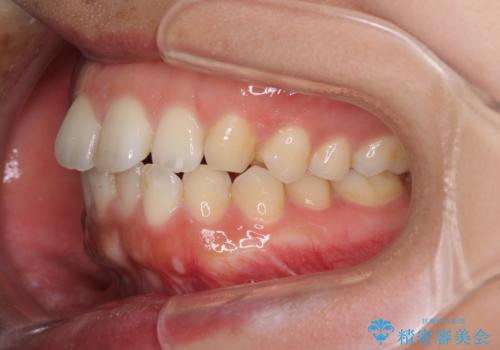

全く目立たないワイヤー矯正 上下リンガル矯正

- 上下の前歯のでこぼこを気にして来院された患者様です。

結婚式が近いこともあり、全く目立たない裏側矯正により口元を整えることとしました。

下顎が左側にずれているため、裏側矯正ということもあり咬み合わせを整えるのに時間がかかってしまいました。